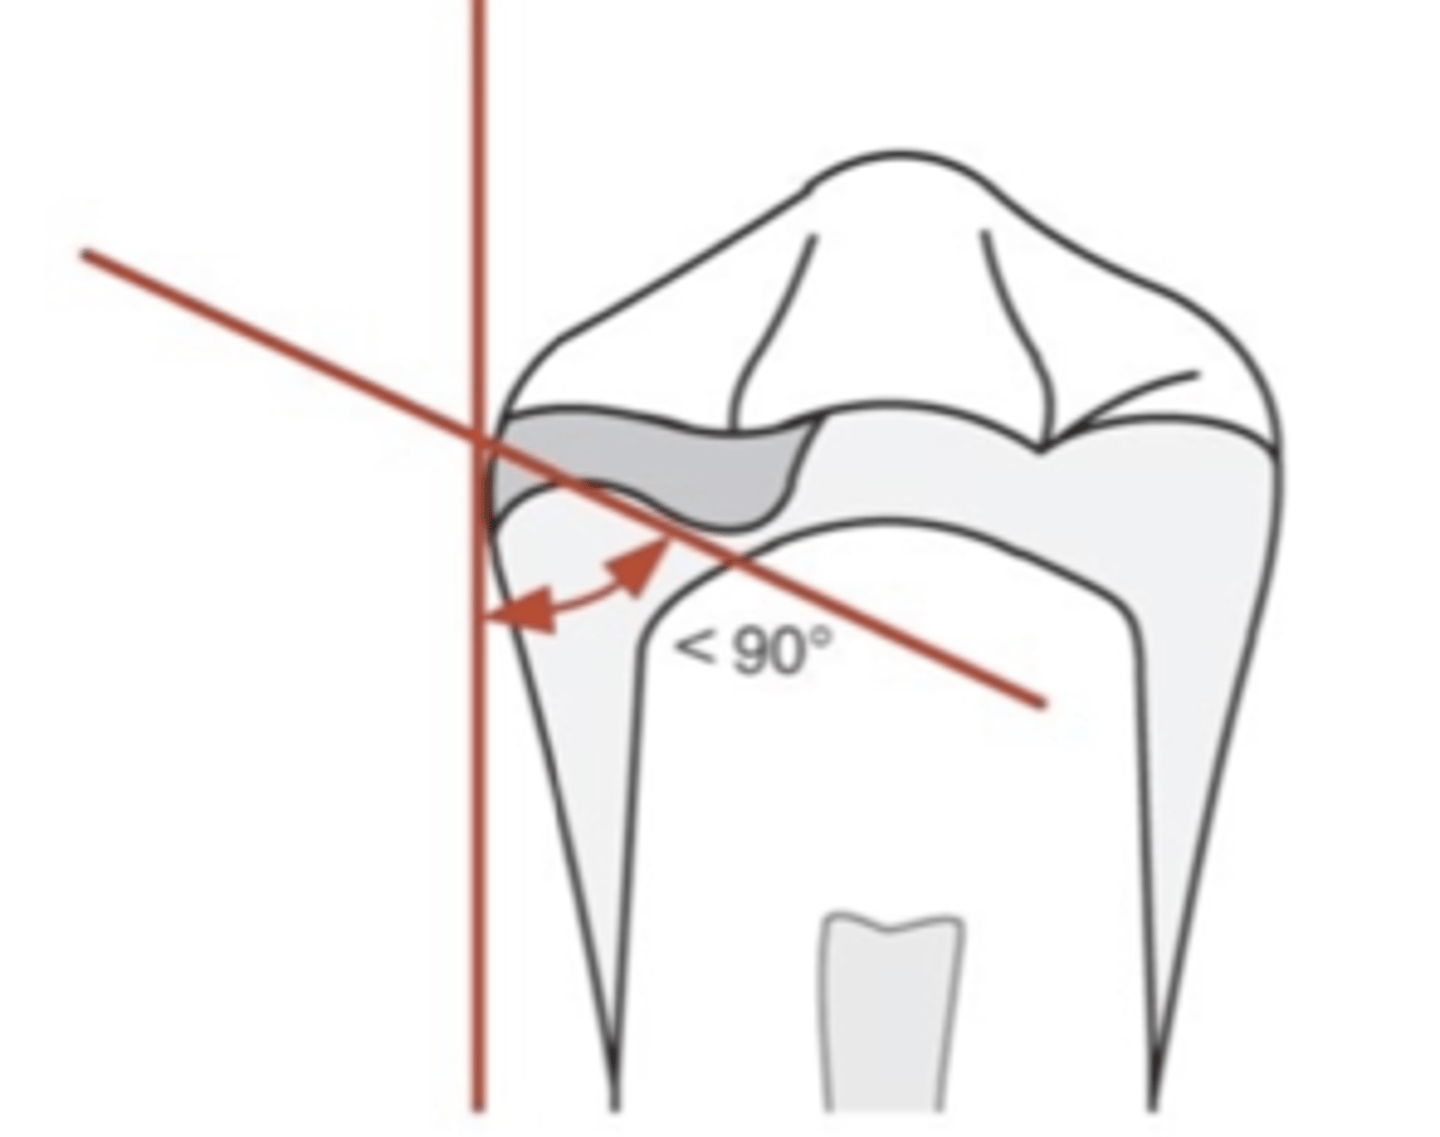

inner

In an occlusal rest, the _______ portion must be located more apically than outer portion near marginal ridge (positivity). May or may not require tooth preparation. If the angle between minor connector and inner portion of rest is ≥90°, occlusal forces will act to slide the rest away from the tooth

Cingulum rest

Similar to occlusal rests, the rest must be made at the correct angulation in reference to the tooth surface to prevent the rest from sliding away from the tooth.